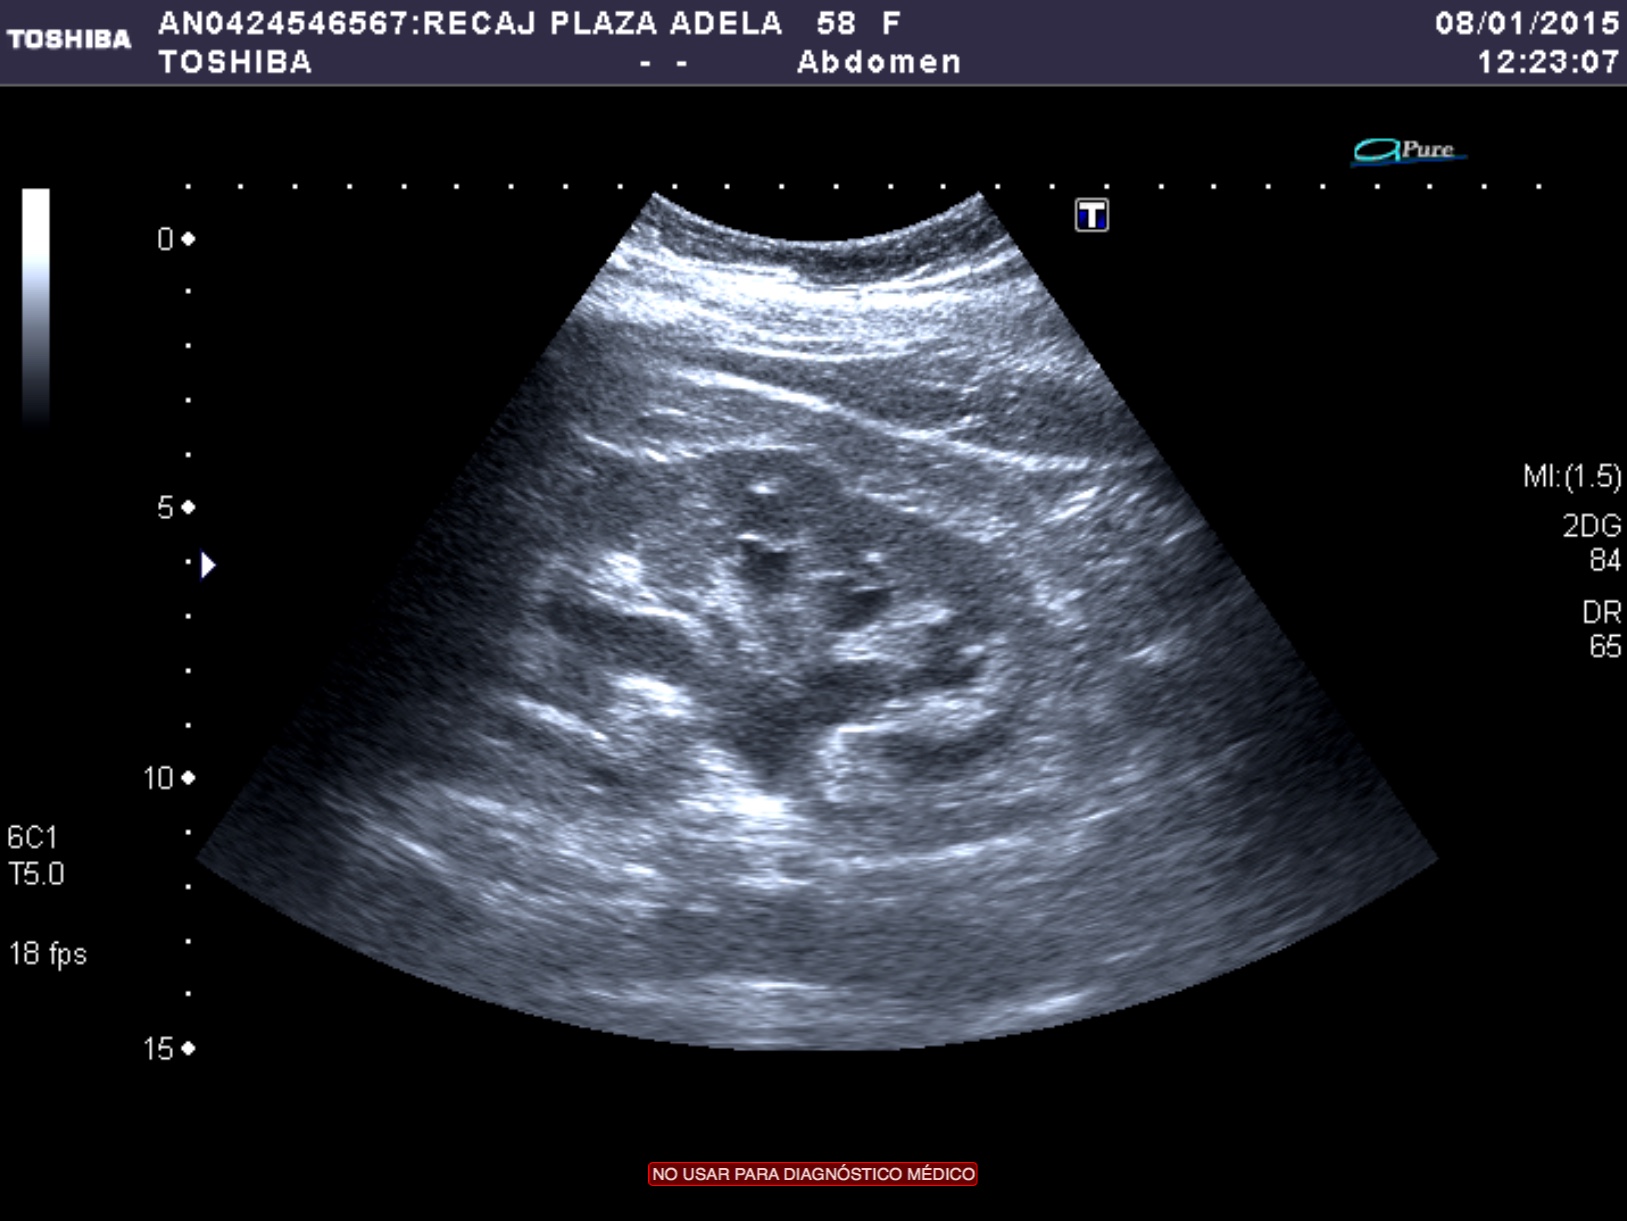

- Ecografía: es una herramienta accesible y se puede usar para una primera valoración de la hematuria. Sin embargo, tiene una sensibilidad del 80% y es poco útil para el diagnóstico de tumores del tracto superior.

Tras el tratamiento de la recidiva y nefrostomía para la hidroureteronefrosis, vuelve acudir al hospital a los 9 meses por episodio de dolor en FD y malestar general. Se realiza una ecografía de urgencias.

Se realiza nueva TC bifásico abdominopélvio y Uro TC.